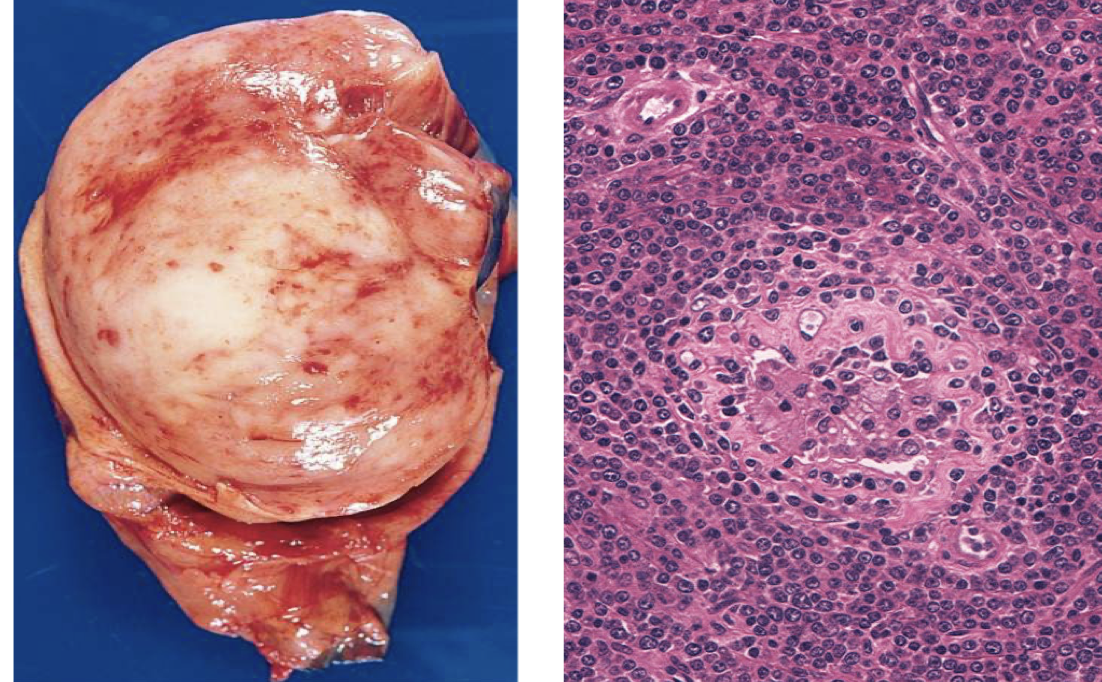

Seminoma

PLAP stain Seminoma